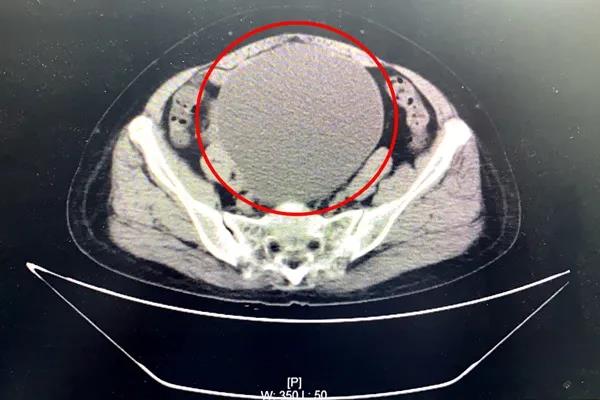

7月13日,63岁的陆阿姨来到幸运轮盘娱乐中心 外科门诊就诊。她自觉6月开始腹部增大明显,并感腹部坠胀不适感。外科检查全腹部CT提示:盆腔内巨大囊性病灶,考虑浆液性囊腺瘤,近20公分大!患者及家属对病情十分担忧。

妇产科顾爱玲主任前来会诊。经检查,患者腹部包块增大明显,盆腔巨大包块已如怀孕近6月大小。顾主任详细问询病史、查体,并再次至放射科与医生共同阅片,考虑患者巨大盆腔肿物瘤良性可能大。她与患者及家属详细沟通了相关病情,逐渐打消了患者及家属顾虑。患者及家属决定留幸运轮盘娱乐中心 进一步诊治。

一般来讲,盆腔巨大肿物,直径达20cm,手术方式会倾向选择开腹手术。但是考虑到患者曾有过2次腹部手术史,一次为17年前因“子宫肌瘤”在外院行经腹全子宫切除术,一次为阑尾切除手术,又盆腔粘连严重,且开腹手术伤口长、恢复慢,会给患者增加痛苦。

7月16日,顾爱玲主任与朱红燕主治医师合作,顺利为患者完成腹腔镜下巨大卵巢囊肿切除、双侧附件切除术、盆腔粘连分解术。手术很顺利,出血少,伤口小,腹部伤口疼痛不明显,术后第一天患者就能下床行走了,并且没有出现并发症。术后肿瘤病理也确认为良性。